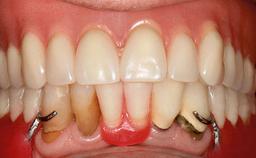

Minimally Invasive Treatment of a Patient in Her Nineties After Removing Implants Affected by Severe Peri-implantitis

A 93-year-old female patient presented in September 2010 with an enlarged swelling on the lingual side of her lower incisors. At the time, she was essentially healthy, except for reduced vision due to bilateral age-related macular degeneration. She had been a heavy smoker (about 30 cigarettes a day) for the past 20 years after becoming a widow. The patient lived at home by herself, with full-time domestic support. An extraoral examination revealed nothing adverse. Intraoral plaque control was anything but ideal, and a soft-tissue tumescence was visible around the lingual aspect of 41–42. Because the nature of the lesion was not clear, a biopsy was carried out that revealed the inflammatory nature of the lesion. The panoramic radiograph showed six irregularly distributed mandibular implants supporting a full-arch prosthesis, with various degrees of interproximal peri-implant resorption. The periapical radiograph revealed interproximal bone resorption mesially and distally to implant 41.